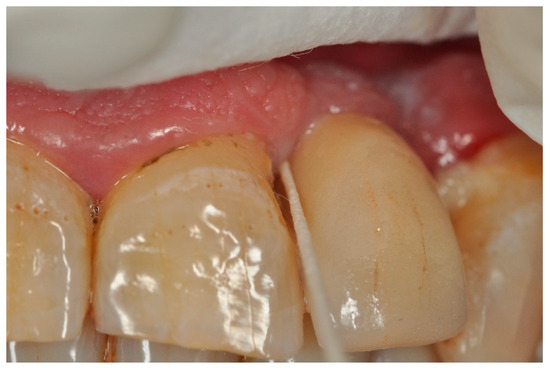

Sampling was carried out beginning in January 2022, with a data collection period of 3 months (Figure 1, Figure 2 and Figure 3).

Briefly, before obtaining the sample, the site was isolated with cotton rolls and air dried. Two sterile paper tips were gently inserted into the deepest probing sites, focusing on 4 different sites, i.e., mesial, distal, buccal, and lingual, and held for 30 s.

Samples contaminated with blood, saliva or pus were discarded immediately. The samples considered suitable were placed in a sterile Dappen Dish, 6 drops of solution A were added, and the dish was shaken for 30 s. The samples were incubated at 95 °C for 6 min, and subsequently, different reagents were applied following the manufacturer’s protocol (Figure 4).

Figure 3. Insertion of paper points in the peri-implant sulcus.

Applsci 13 09621 g003